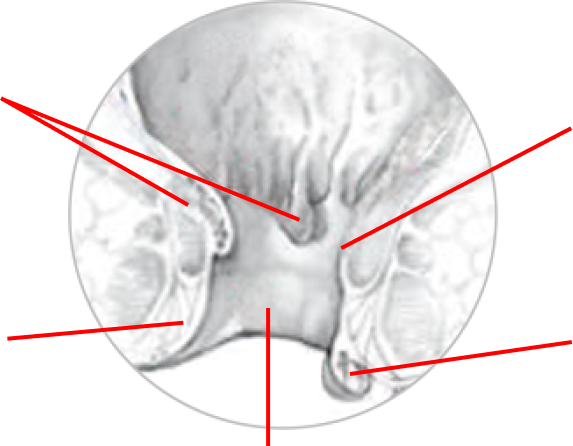

HEMOROIDY

Hemoroidy wewnętrzne

Żyły

Żyły

Hemoroid zewnętrzne

Kanał odbytu

Tak to właśnie z grubsza wygląda. W ostatniej fazie hemoroidy pękają i wypadają… Nic przyjemnego!

Z początku myślałam, że jestem jednym z młodszych przypadków, który wysiedział sobie hemoroidy. Okazało się, że guzki krwawnicze ma KAŻDY, bo pełnią kluczową rolę podczas wydalania. Problem zaczyna się, kiedy przestają prawidłowo funkcjonować; wtedy guzki zbyt się rozciągają i wypełniają krwią, z której następnie nie są w stanie do końca się opróżnić. Z tą wiedzą przyszła też częściowa ulga: to normalna rzecz, a już na pewno dla wszystkich, którzy praktykują siedzący tryb życia.